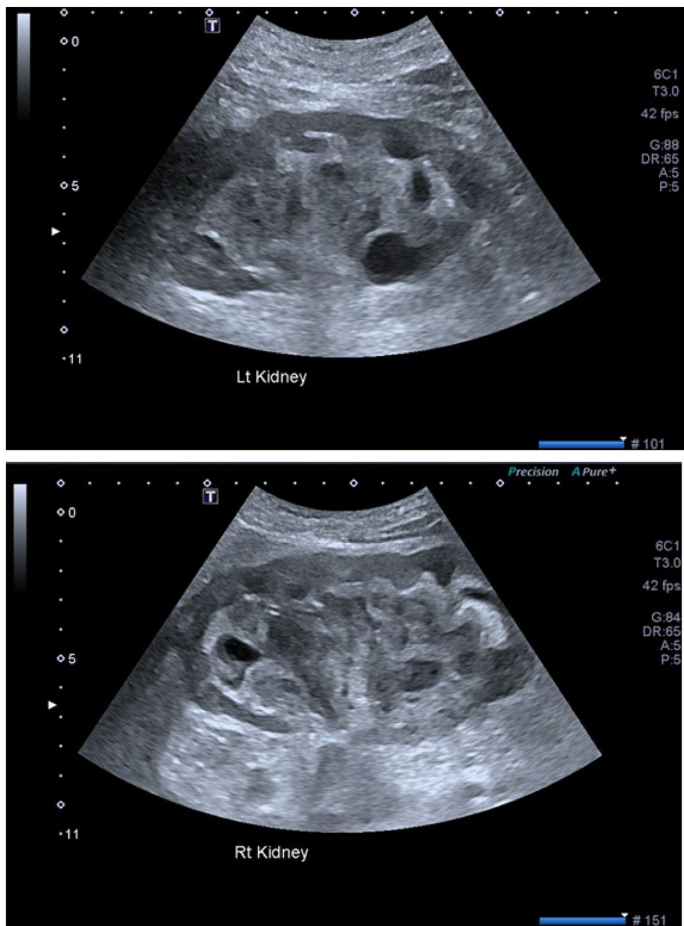

澳大利亚Epworth医院的研究团队在《BMC Nephrology》发表的这例80岁男性病例,为破解这一诊断困境提供了新视角。患者在接受硫鸟嘌呤和羟基脲治疗的CMML基础上突发3期急性肾损伤(AKI),超声检查意外发现双侧集合系统充满扩张性非血管物质——这一特征性表现最终经肾活检证实为LyN的影像学标志。研究采用多学科交叉验证策略,通过组织病理学、特殊染色及免疫组化技术,系统描绘了LyN从实验室异常到影像特征的完整诊断图谱。

超声显示双侧肾脏长度达120mm(同龄标准值),集合系统被非血管性扩张物质填充,伴轻度皮质变薄和皮髓质分界模糊。这一发现突破了既往认为LyN仅表现为非特异性回声增强的认知,首次将集合系统异常与溶菌酶直接关联。